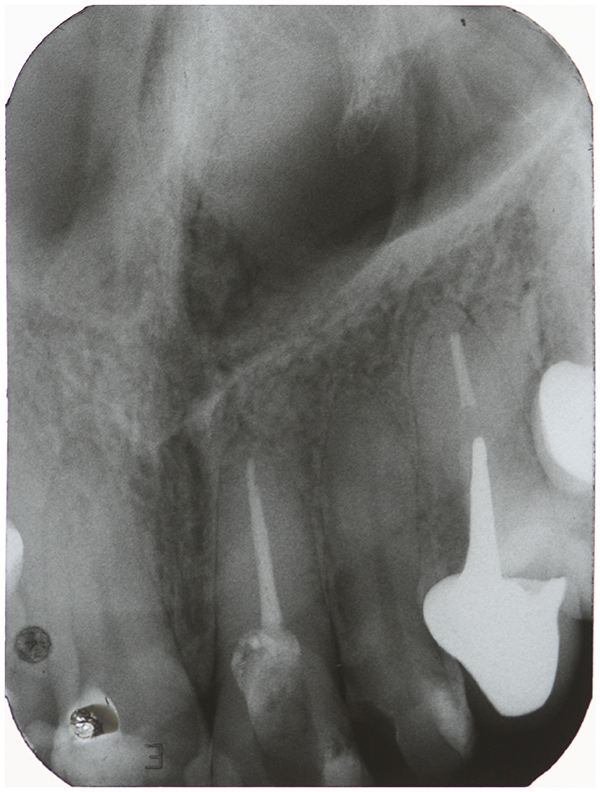

Transurgical Restoration With GlassIonomer Cement As an Option for Root Perforations Case Glass Ionomer Cement Or Composite Composite resin and glass ionomer cements (gics) have been indicated as the restorative materials of choice for these cases 34, 37. Glass ionomers are a mixture of glass and natural acid, usually. Glass ionomer cement can be used as a restorative material in its own right or as a base for a composite resin overlay (sandwich. But for minor temporary. Glass Ionomer Cement Or Composite.